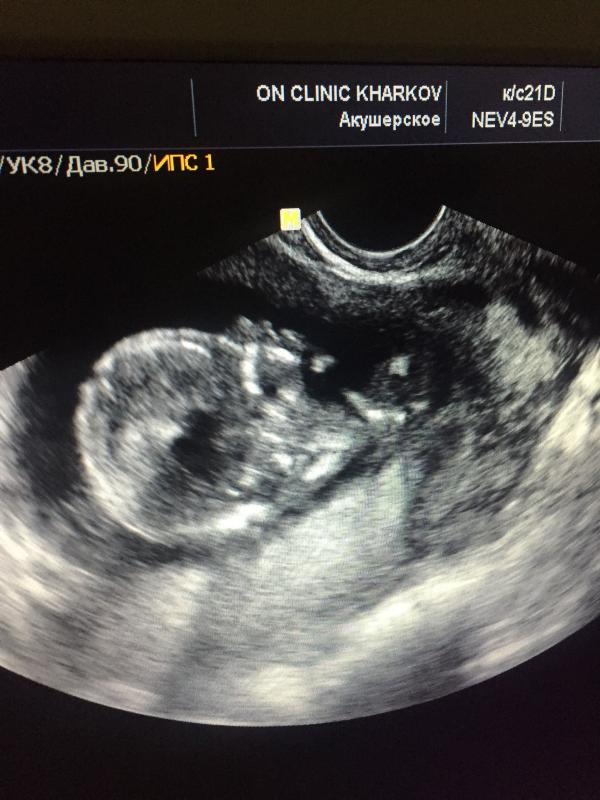

Девчули, я мега нетерпеливая будущая мамаша!!! У нас по УЗИ 14 недель, и побежала я к Погребному надеясь на его славу отличного узиста, узнавать кто же там внутри плавает! Малыш мой долго исполнял, и вертелся и крутился и прыгал!!😂 в один момент даже врач засмеялся и повернув экран ко мне показал как мой разбойник лежит вольяжно закинув ногу на ногу))) Леонид Александрович сказал ему ещё сигары не хватает))😊😊😊😜 и вот тут то мы его и поймали , врач сказал что это конечно не 100 процентов но он ув...